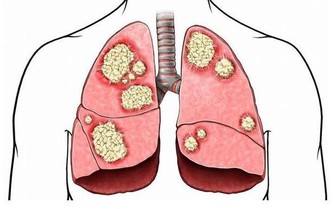

1、高脂血症

花生屬於脂肪含量較高的堅果類食物,而高脂血的人,本身血脂就比較高了,再吃花生的話,容易升高血脂,不利於病情恢復,因為高脂血可能會導致動脈硬化、高血壓、冠心病的出現,所以建議要控制吃花生的量,不要貪吃。